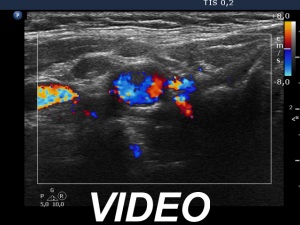

Ultrasonography. The thyroid was echonormal. There was a hypoechogenic nodule in the right lobe. The nodule had numerous punctate echogenic granules.

The echogenic figures are very difficult not to interpret as microcalcifications. Nevertheless, thorough analysis reveals that some of the bright granules has a short tale, and great proportion of these figures are related to ventral tiny hypoechoic areas, probably cysts. Moreover, there are not only echogenic granules but also short echogenic lines within the nodule. Taking all in all, these echogenic figures are very suspicious being microcalcifications.

The ACR TIRADS is the only one which does not use the term 'microcalcification', instead they use the term 'punctate echogenic foci', which includes microcalcifications and short-tail comet-tail artifact. This example stands for the advantage of the ACR terminology.

In such nodules it is to be considered to delay the ultrasound report till the result of FNA. In this patient FNA disclosed benign colloid goiter and there were macrophages on the smear. The latter proved that the nodule had cystic areas. If we take this fact into account, then it can solve our concern about the interpretation of echogenic granules.